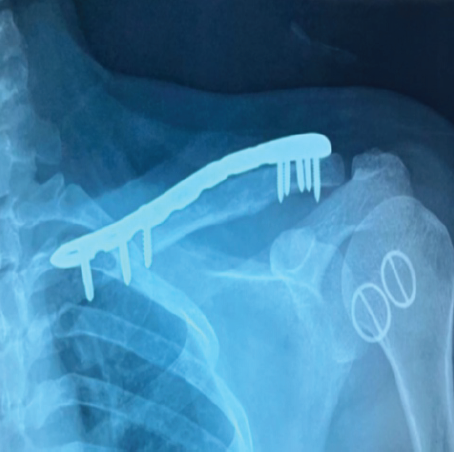

Considering the young age of the patient, the aim of our treatment plan was to salvage the clavicle and preserve the acromioclavicular joint function – which was achieved through extended mechanical and chemical curettage with high speed burr and hydrogen peroxide respectively, cancellous autograft placement from iliac crest, and augmentation plating (Figs. 4, 5, 6, 7).

Figure 6: Augmentation plating with anatomical clavicle plate.

Figure 7: X-ray left shoulder anteroposterior view – immediate post-operative.